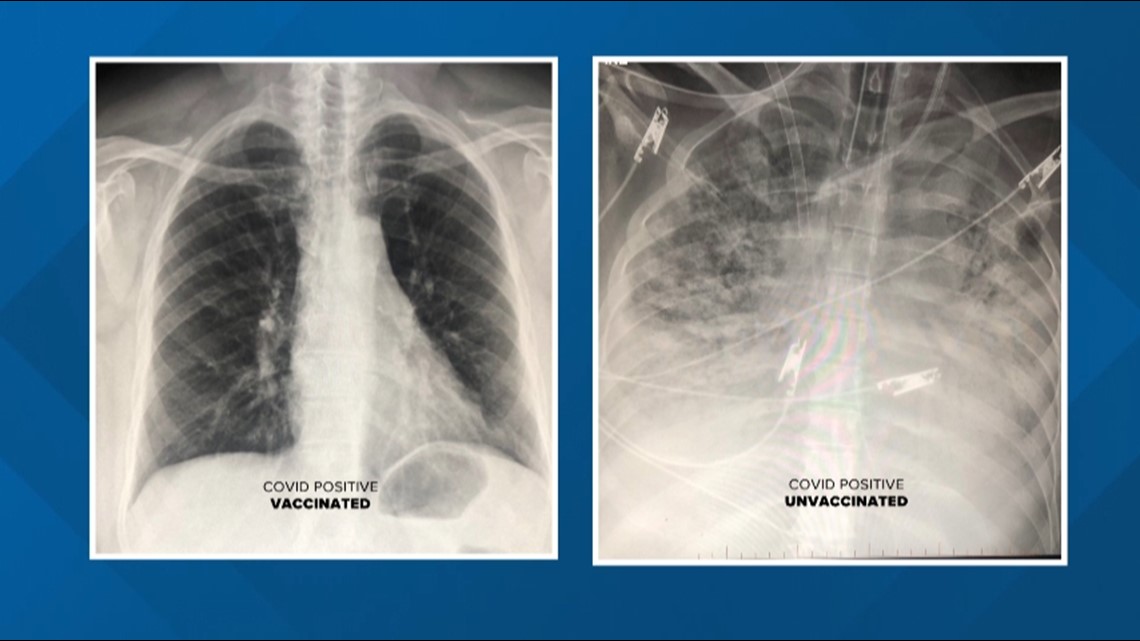

تظهر عمليات المسح بالأشعة السينية الاختلاف الهائل في تأثير الفيروس على رئتي مرضى "كوفيد-19" الذين تم تطعيمهم وأولئك الذين لم يقع تطعيمهم.

وأوضح الدكتور دوراني أن فحوصات المرضى الذين وقع تطعيمهم مع "كوفيد-19" تظهر تدفق المزيد من الهواء، مع تلوين الجزء الأكبر من الرئتين باللون الأسود، ما يعني أنه لا يوجد ضرر يذكر .

وفي المقابل، تظهر صور الفحص من شخص غير مطعم أن الرئتين محتقنتان، ما يحد من تدفق الأكسجين في جميع أنحاء الجسم.

وأضاف الدكتور دوراني: "إذا كان لديك مريض حصل على التطعيم يأتي إلى غرفة الطوارئ مصابا بعدوى غير مسبوقة، ربما يعاني من ضيق في التنفس ونقوم بإجراء فحص بالأشعة المقطعية، فلن يكون بسوء المرضى ذاته كغير المطعمين".

وتابع: "حتى حالات العدوى الخارقة التي ينتهي بها المطاف بالإصابة بالالتهاب الرئوي، فإن فحوصات التصوير المقطعي لم تكن سيئة مثل تلك التي أجريت على المرضى غير المطعمين".

ويمكن للقاحات أن تمنع المرض الشديد والموت لدى غالبية الناس، لكنها للأسف لن تعمل مع البعض. وهذا يعني أن الذين يحصلون على لقاحات ذات جرعتين سيظلون في المستشفى برئتين موبوءتين بـ"كوفيد-19"، ولكن بمستوى أقل بشكل كبير مقارنة بأولئك الذين ليس لديهم أي حماية من اللقاح.

ومن خلال رؤية الصور والأضرار التي يمكن أن يحدثها الفيروس في الرئتين، يوضح الدكتور دوراني: "اللقاح يعمل بشكل جيد للغاية ويمنع الفيروس من التقدم إلى الالتهاب الرئوي أو التسلل إلى الرئتين. وعندما تحصل على جرعة يمكن أن تمرض قليلا، لكن في النهاية يتعرف جسمك عليها، ويهاجمها ولا تدخل المستشفى، ولا يقع وضعك على جهاز التنفس الصناعي، إنه فعال للغاية".